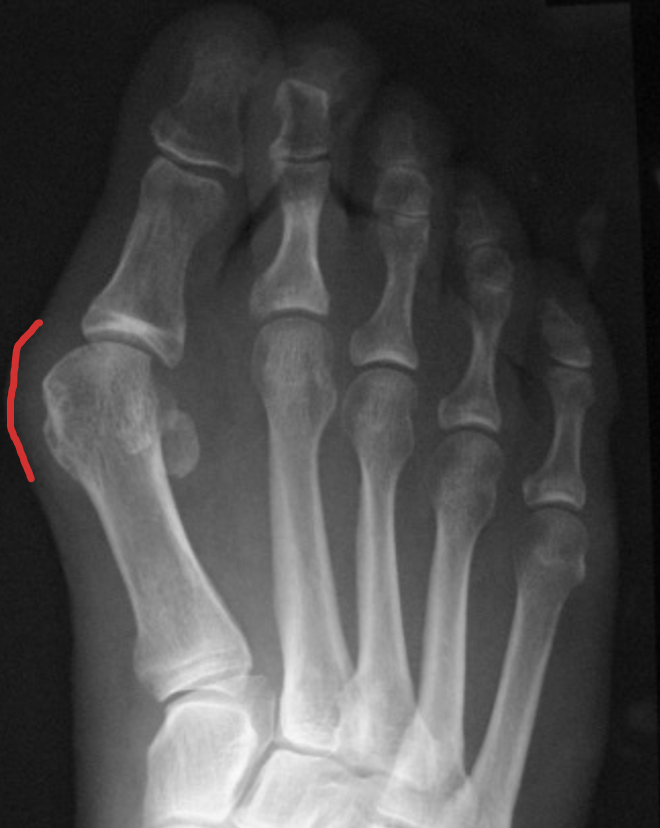

O tão conhecido Joanete, nome popular do hálux valgo, caracteriza-se por uma saliência na região medial da base do dedo grande (hálux), anatomicamente descrita como articulação metatarsofalângica. O aparecimento deste volume ocorre devido a um desalinhamento ósseo, e não pela formação ou surgimento de osso novo, como muitas pessoas pensam. Além disso, outras deformidades, como dedos em garra, pé plano ou outras alterações, podem estar associadas.